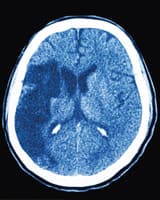

A stroke can be either ischemic (blockage) or hemorrhagic (bleeding). A CT scan or MRI of the brain must be done quickly at a hospital’s emergency department to diagnose what kind of stroke is occurring (about 85% of strokes are ischemic).15,16

Based on brain imaging results, a quick decision must be made whether to implement a clot dissolving drug and/or utilize intracerebral arterial stenting to reverse the blockage causing an ischemic stroke.